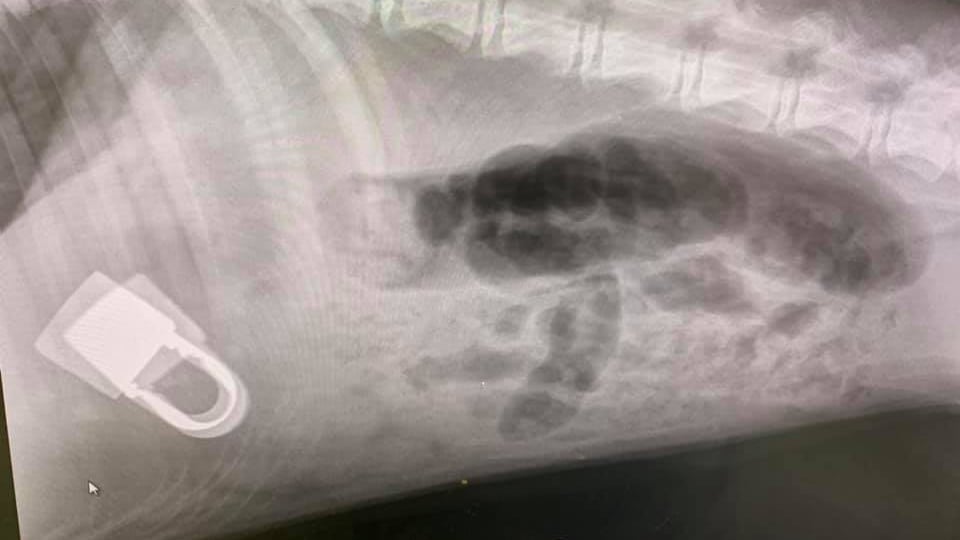

Megan recently spotted the key to the kennel’s padlock in Beau’s mouth. She quickly removed it but realised that the padlock was also missing. Suspecting the worst, she and Jake searched and, when they found no sign of it, they rushed her to Medivet Long Sutton where vet David Iturregui Uria took an X-ray and quickly located the padlock in her stomach. He operated on Beau immediately to remove it and she is now recovering at home.

Medivet vet David Iturregui Uria said: “Beau was lucky that the open padlock did not get stuck in her throat, her oesophagus or her stomach. She needs to stop trying to become the next Houdini!